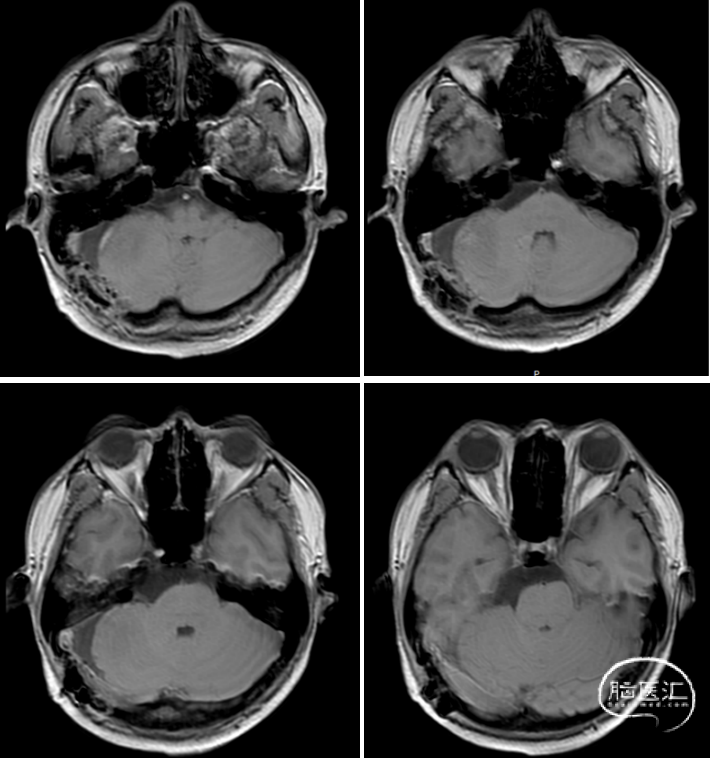

术后MRI